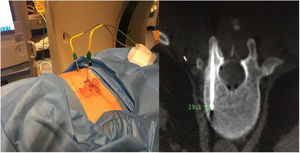

Sixty-one-year-old male, with no history of interest, assessed due to severe hypophosphataemia and treatment-resistant hyperphosphaturia. Clinically he suffered from general incapacitating bone pain and required crutches for walking. The images showed multiple bone lesions and fractures at several levels, with a prominent non-displaced sub capital fracture of the right femur. The PET/CT detected bilateral thyroid nodules with negative PAAF. The Tc-sestamibi marked bone scan presented focal uptake compatible with parathyroid adenoma, guiding diagnosis towards primary hyperparathyroidism (PHPT). A left hemithyroidectomy was performed resulting in normal parathyroid gland. Further analytic tests revealed hypophosphoraemia of 1.2 mg/dl, AF of 402 U/l and FGF23 of 247 U/l (n < 145). This finding guided diagnosis towards PMT, not initially detectable with NMR and PET/CT. A replacement medical treatment was selected, with the patient improving partially clinically and analytically. Due to the levels of FGF23 up to 357,2 U/l an octreoscan with no diagnosis was performed. Finally, repetition of the PET/CT detected an increase in metabolic activity in the right side of the body of L1 (Fig. 1). Following CT-guided needle core biopsy (NCB) a lesion compatible with PMT was diagnosed. Treatment consisted in percutaneous cryotherapy of the lesions guided by CT and simultaneous neurophysiologic control (Fig. 2). Phosphorous levels in blood and urine and FGF23 levels have normalised over time.

Definitive PMT treatment consists in surgical resection,28 which is followed by a fast analytical improvement and the consequent regression of symptoms. Cases 2 and 3 were surgically treated with extended resection. Case 1 opted for percutanoue ablation with CT-guided cryotherapy under neurophysiologic control. This technique is widely used for the percutaneous treatment of benign mesenchymal tumours, including PMT.29–32 Based on the experience of our group, we believe that this therapeutic model has major advantages in both the eradication of the tumour and also in minimising complications and aiding patients’ recovery when anatomical locations are complex.